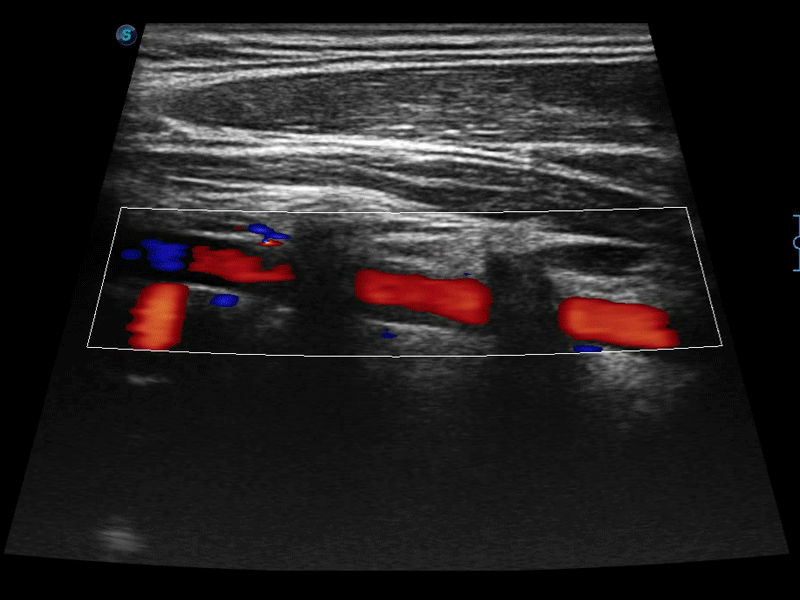

临床图像

• SR Flow高分辨率血流成像技术

高分辨率血流成像技术提高了对低速血流信号的检测能力。在提高空间分辨率的同时,也克服了血流外溢现象,为用户提供更加真实的血流动力学信息。

• 实时宽景成像技术

通过色彩血流和实时宽景相结合,可观察到完整的静脉或动脉的血流,方便医生检查。实时扫查过程中,如有任何操作失误也可以很容易地进行回扫擦除,而不会中断扫查。